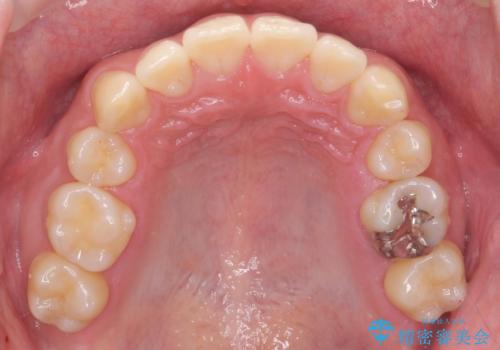

矯正後8年目になりますが、並びも綺麗に保持でき、また上下の歯がさらにしっかり咬んできているのがわかります。

定期的にメンテナンスにきていただき、特に歯の健康状態にも問題がありません。

さしたる問題もなく、半年~1年に一度のメインテナンスにお越しになっている患者様です。保定装置については、慣れれば習慣化するためさほど負担ではありません。

矯正をしなくても起こる下の前歯のがたつきも予防でき、若々しい歯並びを維持することができます。

当院は矯正治療後も長くお付き合いいただき、健康で綺麗な歯並びを保つお手伝いをさせていただいております。